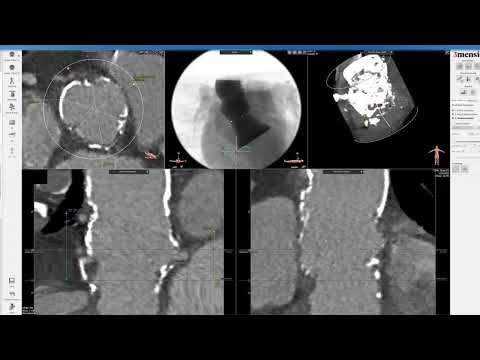

3Mensio CT Pre-case planning: Redo-TAVR with Prior Evolut PRO